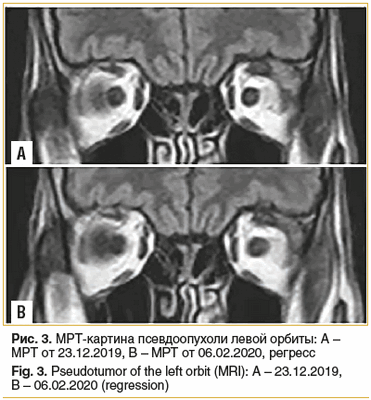

МРТ головного мозга, орбит 24.12.2019 — в области утолщенного сухожилия верхней прямой мышцы слева визуализируется участок с гипо-изоинтенсивным сигналом, мягкие ткани века, области вокруг слезной железы утолщены, сигнал не изменен. Патологии зрительных нервов не отмечено. Заключение: подозрение на миозитическую псевдоопухоль левой орбиты (рис. 3 А).

В результате терапии в течение 2 мес. отмечена существенная положительная клинико-рентгенологическая динамика в состоянии пациента. При контрольной МРТ головного мозга, орбит от 06.02.2020 (рис. 3 В) в сравнении с МРТ от 23.12.2019 отмечается нормализация толщины сухожилия верхней прямой мышцы слева; мягкие ткани века, области вокруг слезной железы по интенсивности сравнимы с противоположной стороной, сохраняется некоторое утолщение верхнего века.